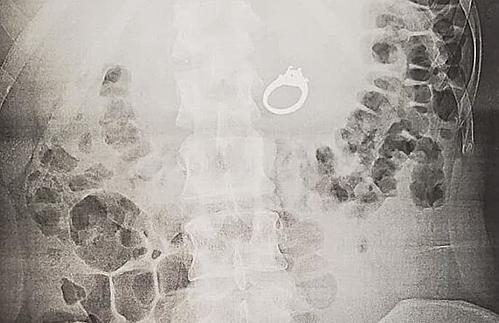

Tại bệnh viện, Evans phải khó khăn để giải thích sự cố hài hước và khó tin của mình. Các bác sĩ khuyên nên phẫu thuật thay vì để nhẫn ra tự nhiên. Cô được gây mê và nội soi để lấy nhẫn ra.